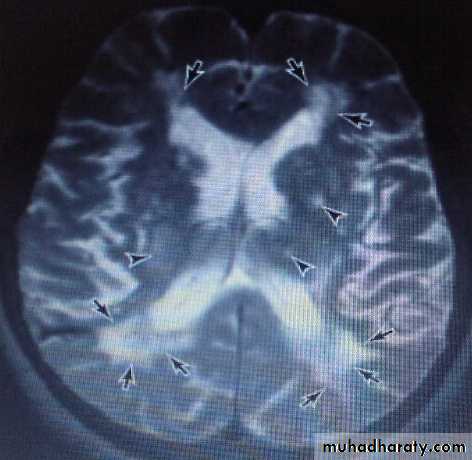

The MRI in multi-infarct dementia may show multiple large cortical or small subcortical lacuncies.

Extensive areas of low density in subcortical white matter are seen in Binswanger disease (subcortical arteriosclerotic encephalopathy), which may be a related condition but with insidious onset & slowly progression, features that distinguish it from multi-infarct dementia, though some patients show stepwise progression.

MRI is more sensitive than CT for detecting these abnormalities.